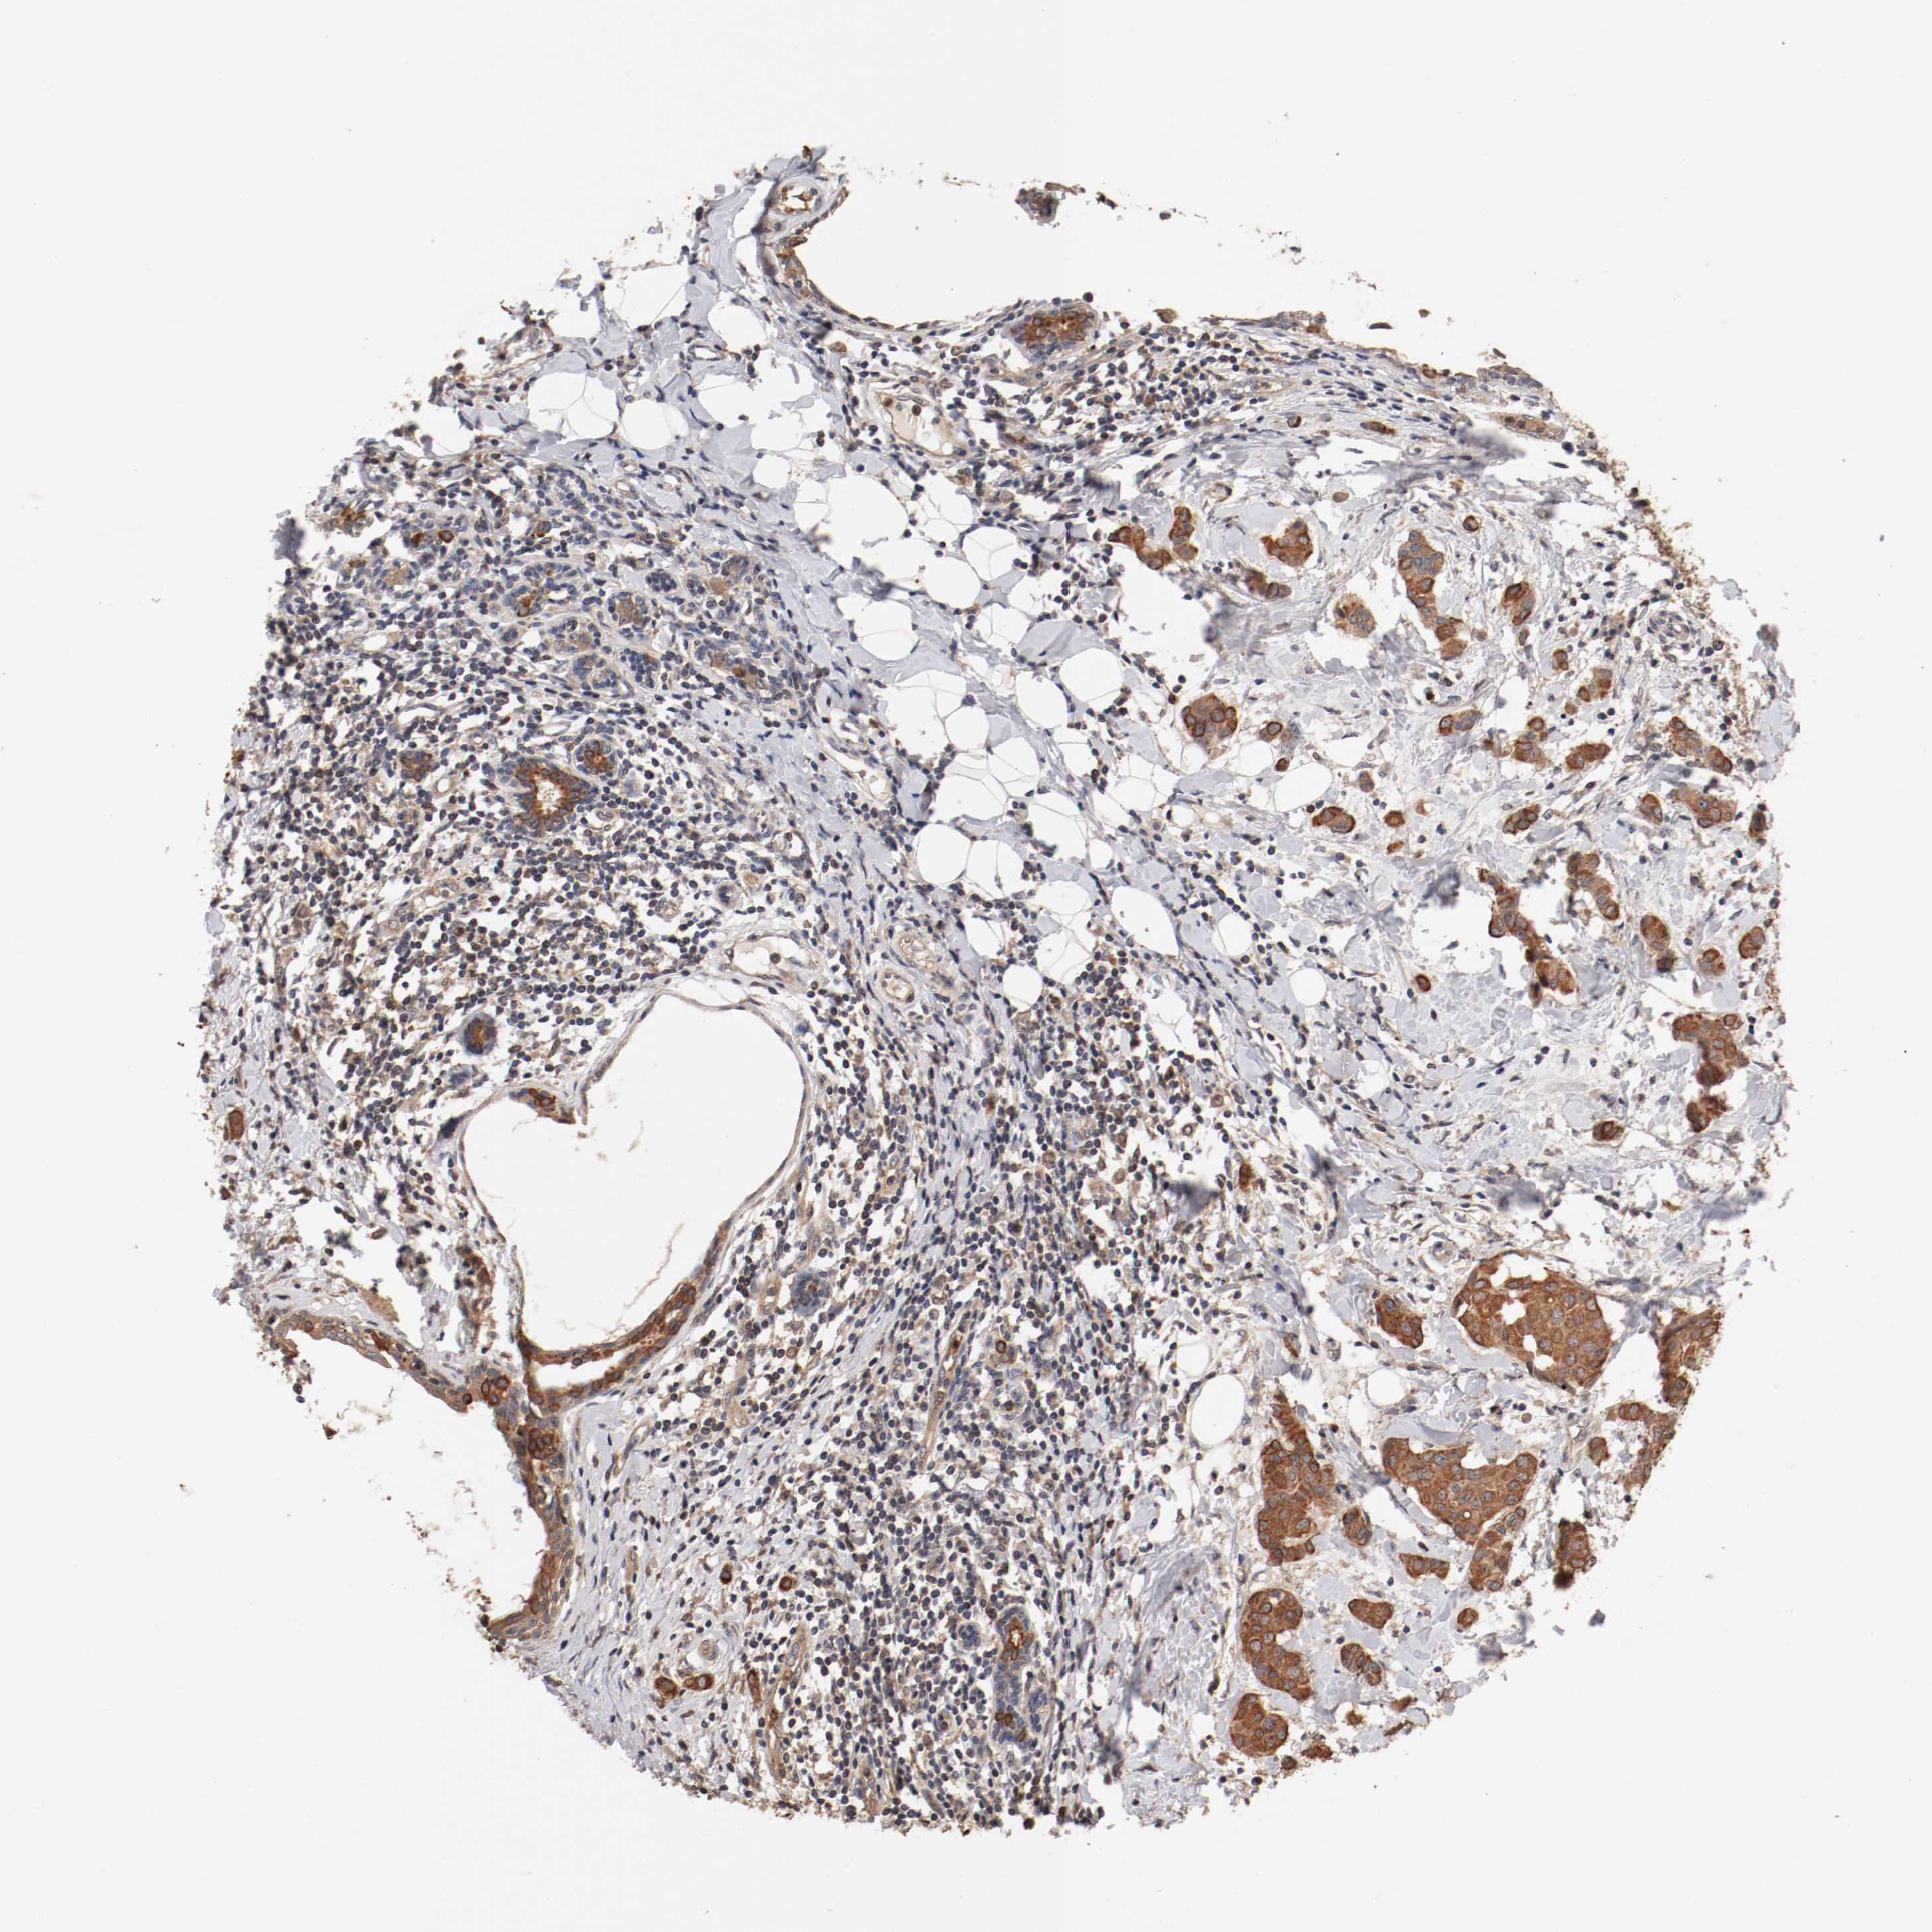

CANCER BREAST CANCER Show tissue menu

BRCA TCGA BRCA VALIDATION PROTEIN EXPRESSION